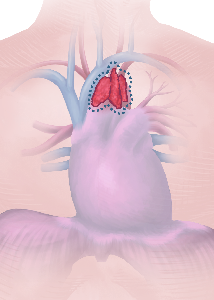

Detailreiche Fotografien aus der medizinischen Praxis ergänzen die Texte; moderne, genaue,

wissenschaftliche Zeichnungen geben Einblick in die Anatomie und die Funktion der Lunge und

anderer Organe.